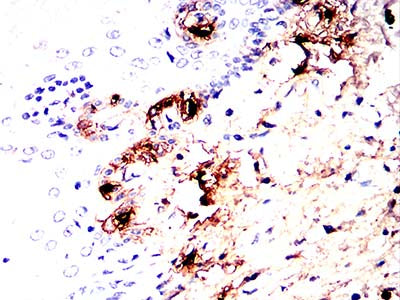

Immunohistochemical analysis of paraffin-embedded human cervical cancer tissues using TPSAB1 mouse mAb with DAB staining.